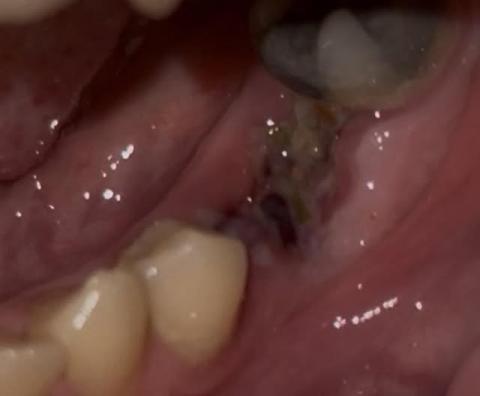

Severe Lower Molar Decay: Urgent Restoration and Gum Care Needed

Case Type: Advanced Dental Caries and Calculus Accumulation

Full Analysis and Diagnosis

Upon examination, the posterior molars exhibit:

Extensive caries (tooth decay) on both left and right sides.

Possible pulp involvement — dark discoloration and cavity penetration indicate the decay may have reached the pulp chamber.